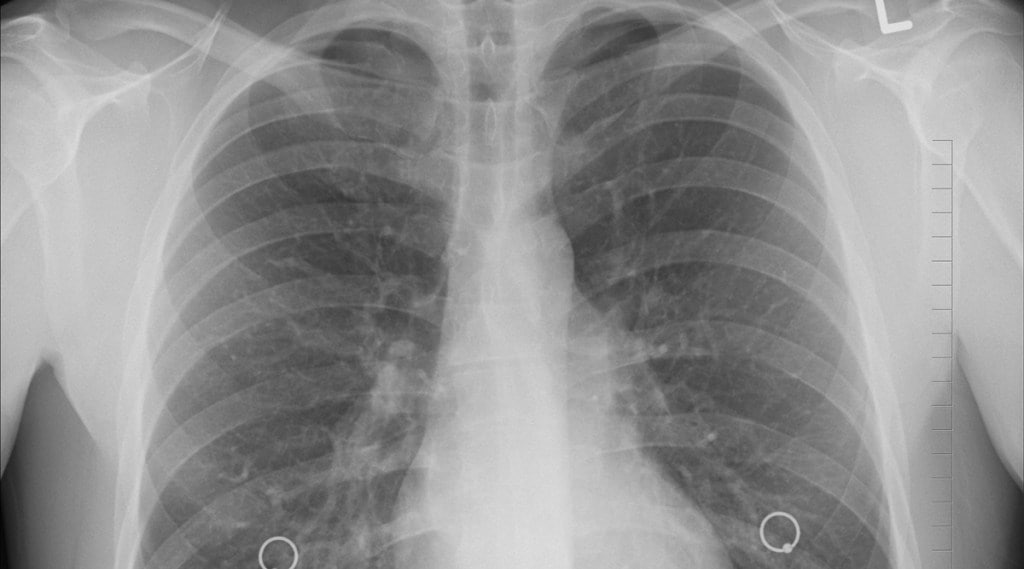

Qure.ai, a health-tech firm, builds AI-powered solutions focusing on pulmonary and neurocritical care to deliver better care for patients. The software known as qXR software can detect 30 critical lung abnormalities in under a minute. (Image Credit: Pixabay)

Qure.ai, a health-tech firm, builds AI-powered solutions focusing on pulmonary and neurocritical care to deliver better care for patients. The software known as qXR software can detect 30 critical lung abnormalities in under a minute. It can also quantify the infection, giving doctors and other healthcare workers real-time insights into disease progression, the company claims.